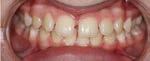

SPINA BIFIDA IS A CONGENITAL CONDITION AFFECTING THE SPINAL CORD AND POSES SIGNIFICANT CHALLENGES FOR PATIENTS AND THEIR FAMILIES. IT OCCURS WHEN THE SPINAL CORD DOES NOT DEVELOP PROPERLY DURING FOETAL DEVELOPMENT. THIS CONDITION CAN LEAD TO VARIOUS IMPAIRMENTS, INCLUDING DIFFICULTIES WITH MOBILITY, BOWEL AND BLADDER DYSFUNCTION, AND LOSS OF SENSATION.

JULY.AUG 2023 8